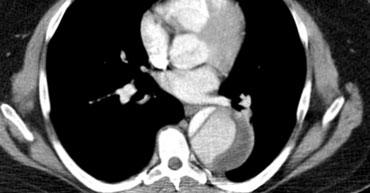

TRÁI: Bóc tách Type A với vạt nội mạc rõ ràng thấy trong quai động mạch chủ. PHẢI: Bóc tách Type B. Điểm vào phía xa động mạch dưới đòn trái.

Các hình ảnh bên trái đều cho thấy bóc tách type A với điểm vào rõ ràng ở động mạch chủ lên.

Lòng thật được bao quanh bởi lòng giả, lòng giả lớn hơn và chèn ép quanh lòng thật do áp lực tâm thu liên tục.